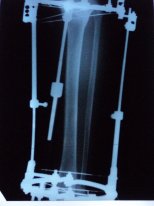

Добрый вечер! Отправляю снимки. Жду ответа.

Вложения

5.JPG

3.JPG

1.JPG

Галина, вечер добрый! Качество снимков ужасное, детально судить о возможности снятия аппаратов, не представляется возможным. Для перестраховки приезжайте в клинику через 2 недельки. Если делать рентген, то надо снимать голень с захватом коленного сустава в 2-х проекциях.